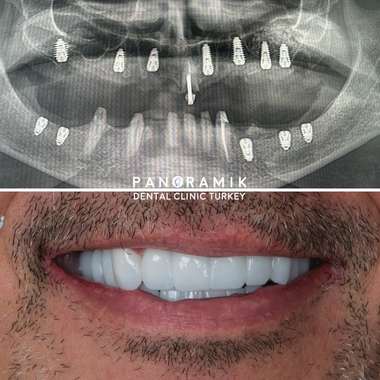

Dental implants are artificial tooth roots placed when teeth are missing. You can also define implantation as the artificial replacement of lost tooth roots. Many people with missing teeth face numerous functional and aesthetic problems. Implants can also be placed if the last teeth in the jaw are missing and a fixed prosthesis (such as a crown or bridge) cannot be fabricated.

With implanted teeth, the patient can regain their previous comfort in terms of functionality and aesthetics in everyday life.